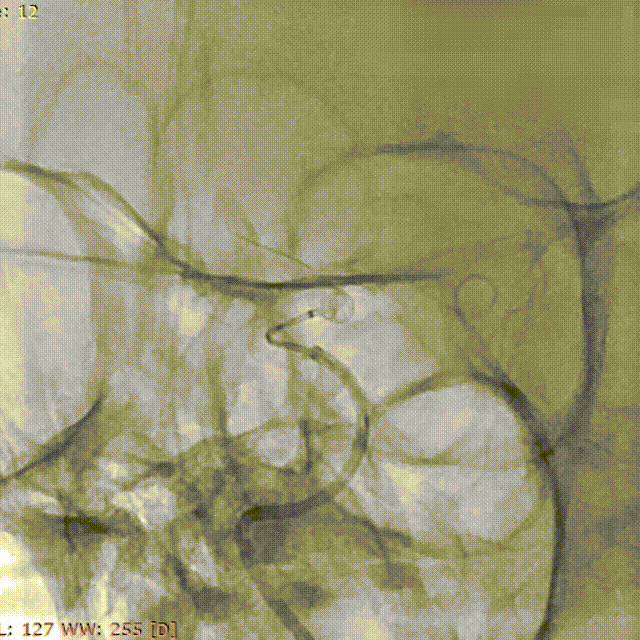

微导丝带017 Accessway微导管上高至远端。

第一枚2*20支架通过017支架微导管到位。

支架远端打开。

支架远端打开情况。

支架中段打开,过50%释放标记点。

造影显示支架整体打开良好。

支架完全释放。

微导管沿推送杆通过支架,撤出推送杆,保留通路。

造影显示支架打开良好,准备桥接第二枚支架。

第二枚3*25支架沿017支架微导管上高。

第二枚支架远端释放。

第二枚支架释放至中段。

中段释放适当推挤系统,保持贴壁良好。

中段释放后造影。

继续释放支架。

继续释放支架,造影观察贴壁良好。

完全释放支架。

支架微导管沿推送导丝上高并将推送导丝撤出。

术后即刻造影。